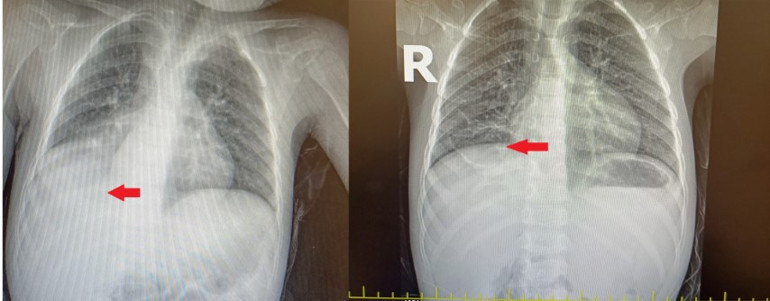

Başakşehir Çam ve Sakura Şehir Hastanesi Çocuk Cerrahi Kliniği’nden Opr. Dr. Mehmet Çakmak, "Acil servisteki doktor arkadaşlarımızın muayenesi sonrası çekilen akciğer röntgeninde, sağ alt bölgede sıvı birikimi nedeniyle bize danıştılar. Hastanın öyküsünü annesinden tekrar dinlediğimizde, şikayetlerinin 1 yaşında kardeşleriyle otururken karpuz çekirdeğini ağzına götürmesi sonrası başladığını öğrendik. O zaman çekilen akciğer röntgeninde herhangi bir patolojik bulguya rastlanmayınca, 3 yıl boyunca semptomlarının ara ara iyileşmesi nedeniyle de daha çok astım, bronşit pnömoni gibi teşhisler düşünülmüş ve buna yönelik tedaviler verilmiş. Çünkü normalde yabancı cisim aspirasyonlarında, semptomlar gerilemez. Biz, annesinin verdiği öyküyü dinleyince tomografi çektik ve sağ akciğer alt bölgeyi havalandıran bronşun, bir yabancı cisimle tıkalı olduğunu tespit ettik. Yaptığımız bronkoskopide bir karpuz çekirdeğine rastladık ve işlem esnasında karpuz çekirdeğini çıkardık" dedi.

Dr. Çakmak, kendilerini en çok, bu kadar uzun süre geçmiş olmasına rağmen karpuz çekirdeğinin nefes borusunda mukoza tabakasının içine gömülmeden kalabilmiş olmasının şaşırttığına değinerek sözlerini şöyle sürdürdü: "Çünkü üzerinden uzun süre geçmiş yabancı cisim aspirasyonlarında, vücut bir nevi kamufle edebilmek adına, yabancı cismin mukoza tabakasının altına gömülmesine sebep olur. O bölgedeki akciğer lobu atelektazi dediğimiz çökmeye doğru ilerlemişti. Eğer cismi çıkarmasaydık, o akciğer lobu tamamen söner ve kullanılamaz hale gelirdi. Biz yabancı cisim aspirasyonlarında en çok kuruyemiş ve fındık çıkarıyoruz. Kuruyemişlerin yüzde 70-80'ini fındık oluşturuyor. Bronkoskopide bizi en fazla zorlayan yabancı cisim ise leblebi tarzı şişen ve ilerleyici tıkanıklığa sebep olan kuruyemişler. Bunlar kolaylıkla parçalanıyor, soluk borusuyla akciğerin çeşitli dallarına yayılabiliyor. O da işlemin uzamasına sebep oluyor. Bir hastamızın sağ soluk borusundan iki tane beton çivisi çıkarmıştık. Yine yakalara takılan çengelli iğnelerin aspirasyonu oldukça riskli. Ayrıca toplumumuzda yaygın olarak kullanılan ve diş ağrısını geçireceğine inanılan kehribar kolyesi de bebekler için oldukça tehlikeli. Biz, Çam ve Sakura Çocuk Cerrahisi Kliniği olarak Avrupa yakasında oldukça fazla hastaya bronkoskopi yapıyoruz. Çeşitli kongrelerde de yayınladığımız çalışmalarda, aile öyküsünde yabancı cisim aspirasyonu şüpheli hastaların yaklaşık yüzde 90'ında sonuç pozitif çıkıyor. O nedenle ailenin dikkati burada çok önemli."

Ailelerin çocuğun boğazına bir şey kaçtığında ağır bir belirti yoksa ilk başta durumu önemsemeyebildiğine dikkat çeken Dr. Eres, "Çocuklarının başına geldiğinde acil servise başvurmakta da gecikiyorlar ya da hastalar bazen acil serviste akciğer filmleri çekiliyor, solunum bulgularına bakılıyor, muayeneleri yapılıyor, her şey normal çıkıyor. Nefes sıkıntısı da olmayınca, aile de bu yönde bir öykü vermediyse; atlanabiliyor. Oysa tekrarlayan solunum yolu enfeksiyonları, geçmeyen hırıltı, tedaviye yanıt vermeyen astım bulguları varsa, aileler geçmişe yönelik düşünmeli ve o konuda bilgi vermeli. Geçmeyen öksürüklerde, tedaviye yanıt alınamayan astım olgularında bronkoskopi yapılarak yabancı cisim aspirasyonu ve diğer organik patolojiler ekarte edilmeli. Bizim vakamızda da 3 yıl geçmiş, Çocuk Cerrahisi ekibini kutlamak gerekiyor gerçekten. Çünkü 3 yıllık bir geçmişi olan çekirdek parçasını o doku içerisinden seçip çıkarmak, ameliyata gerek kalmadan hastayı tedavi edebilmek gerçekten çok zor bir işlem.ö Anne Maryam Majzoub da ilk kez 3 yıl önce öksürük şikayetiyle doktora gittiklerini, ancak akciğer filmleri temiz çıkınca enfeksiyon sanıldığını, oğlunun öksürüğünün hiç geçmediğini söyledi ve “Ateş oluyordu sürekli. Daha sonra bir doktor astım teşhisi koydu. Torba torba ilaç kullandık ama hiçbir fayda görmedik. Geçen hafta yine şikayetleri artınca buraya geldik. Acile başvurduk. Sonra Çocuk Cerrahi ekibi gördü bizi ve çekirdek kaçtığını buldular" ifadelerini kullandı.